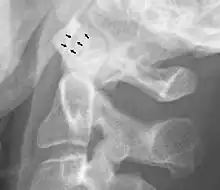

Abnormal widening

A widening of the atlanto-axial joint, as measured between the posterior surface of the anterior arch of atlas and the front of the odontoid process, indicates an injury to the transverse atlantal ligament.[6] Normally, this atlanto-dental distance is less than 2 mm, sometimes a maximum of 3 mm is accepted in men and 2.5 mm in women.[6]